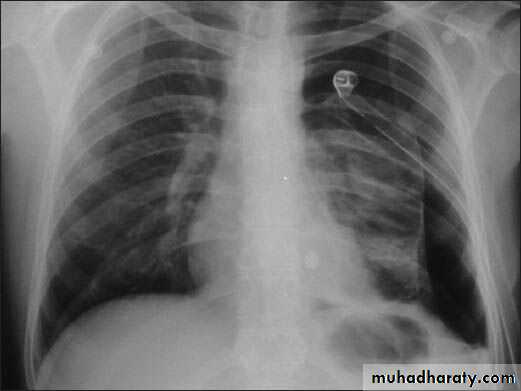

Severe dyspnea with shock

Hemopneumothorax